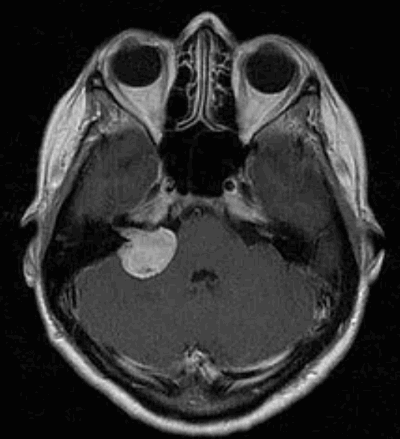

Наиболее информативным методом выявления вестибулярных шванном является МРТ головного мозга с контрастным усилением в режиме Т1 и Т2. Это исследование позволяет определить размеры опухоли, наличие перитуморозного отека, наличие признаков окклюзионной гидроцефалии, которая может быть следствием сдавления опухолью IV желудочка. Кроме этого МРТ позволяет провести дифференциальную диагностику с другими опухолями схожей локализации (чаще с менингиомой задней грани пирамиды височной кости). Еще одним стандартом диагностики является КТ в костном режиме. Независимо от снижения слуха стандартом является проведение аппаратной аудиографии.

Сканирование головы: если другие тесты показывают, что у пациента может быть вестибулярная шваннома, для подтверждения диагноза используется магнитно-резонансная томография (МРТ). МРТ использует магнитные поля и радиоволны, а не рентгеновские лучи для создания подробных изображений мозга. Томография показывает «срезы» мозга, которые можно объединить для создания трехмерного изображения опухоли. Часто пациенту вводят контрастный краситель. Опухоль впитывает больше красителя, чем нормальная ткань мозга, и будет четко видна на сканировании. МРТ обычно показывает опухоль во внутреннем слуховом проходе.

На магнитно-резонансной томографии с гадолинием в аксиальной проекции в режиме Т1 визуализируются двусторонние вестибулярные шванномы,

ассоциированные с НФ2, сдавливающие ствол головного мозга и смещающие его в сторону от срединной линии.